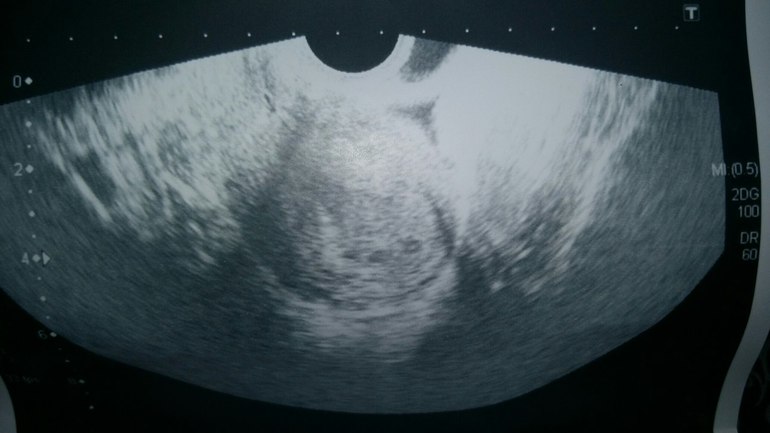

Девочки, всем привет! Может кто помнит, я тут тесты свои выкладывала и очень многие поддерживали меня, рассматривая со мной еле заметного призрака.)) Спасибо Вам! Потом тесты ярчали, полоски сравнялись. ХГЧ не сдавала. Сегодня получается примерно 20 ДПО. И мы только пришли с УЗИ! Новость первая -беременность есть! И она маточная! Нам 3 недельки по УЗИ. Новость вторая- под вопросом двойня... Фото с УЗИ прилагаю, думаю, рано еще о чем-то говорить. Вы как думаете, что видите? Врач сказала, что ей самой интересно и контроль через 10 дней. Новость третья- не очень хорошая- поставила угрозу. Вот глядя на снимок, не могу понять, как и где она это определила... в итоге назначили Фемибион 1, Магне б6, Дюфастон аж 4 табл. в день. Не много ли??? Так не хочется мне на таблетках сидеть. а если вдруг что... ТТТ. может угроза из-за того, что дочку много таскаю... Что делать, не знаю...

и фото с узи

Это так на снимке получилось, на экране было отчетливо 2-е горошинки.

может так на снимке просто получилось, на экране отчетливо было видно 2) в общем, тайна раскроется дней через 10)))